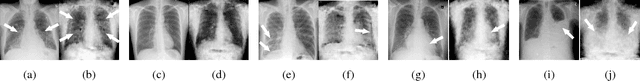

Abstract:Medical datasets are often highly imbalanced with over-representation of common medical problems and a paucity of data from rare conditions. We propose simulation of pathology in images to overcome the above limitations. Using chest X-rays as a model medical image, we implement a generative adversarial network (GAN) to create artificial images based upon a modest sized labeled dataset. We employ a combination of real and artificial images to train a deep convolutional neural network (DCNN) to detect pathology across five classes of chest X-rays. Furthermore, we demonstrate that augmenting the original imbalanced dataset with GAN generated images improves performance of chest pathology classification using the proposed DCNN in comparison to the same DCNN trained with the original dataset alone. This improved performance is largely attributed to balancing of the dataset using GAN generated images, where image classes that are lacking in example images are preferentially augmented.